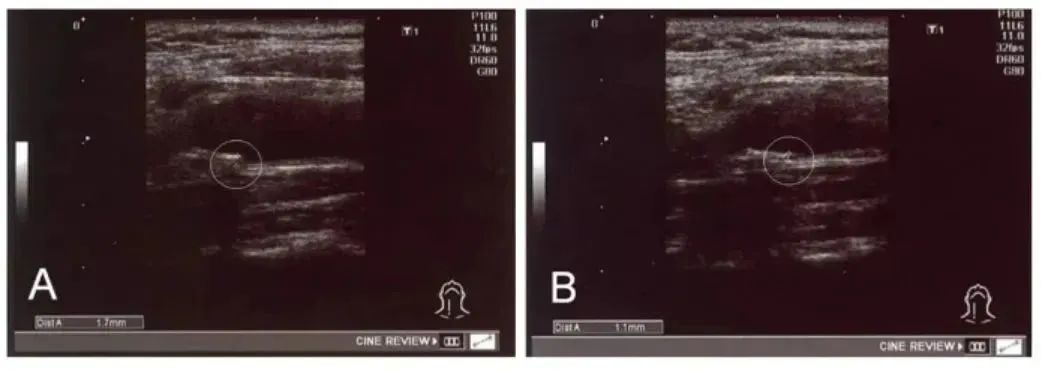

间充质干细胞可分化为脂肪细胞以及肝细胞,它们能帮助调节血脂代谢,拉低血脂水平。研究表明,一名 56 岁男性患者颈总动脉内膜中层厚度为例,MSC治疗前 (a) 和治疗后 (b) 结果显示,治疗后近 4 个月,例如胆固醇、低密度脂蛋白和甘油三酯水平降低,内膜中层厚度从 1.7 毫米减少至 1.1 毫米。